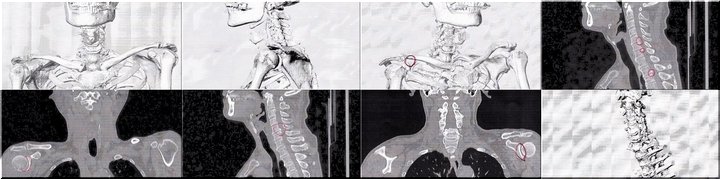

数日前に右腕に激痛が走り、慌てて主治医行きとなりました(^-^;

数日前でしたか…右腕に何となく違和感を感じておりましたが、別に気に掛けておりませんでしたGONsanです。

が、翌日には激痛が走り慌てて主治医行きとなりました(^-^;

とりあえずCTスキャン。

で、頂きましたのが、その一部のこれらの画像なんです(^.-)☆

特に痛みの原因となるようなモノは見当たらず、強いて言えば『老化現象』との事でありました。

痛み止めとシップ薬で痛みが取れなければ、次はMRIとの事でありました(^-^;

…と、こんな記載がWEB上にありましたけど、痛みが取れませんから渋々MRI検査も受ける事に致しました。

と言う訳で、本日がそのMRI検査の実施日でありました。

主治医のクリニックではMRI検査は出来ませんから、紹介先の病院で実施。そしてそのデータを主治医に持参。

どんな結果なのか分かりませんけど、聞くのが恐い感じも致します。

金曜日の到来が、何となく憂鬱に感じられてなりませんGONsanなのであります。

それにしましても、右腕に痛みを抱えて日々過ごしますのは、結構辛いモノではありますねぇ(^-^)//"